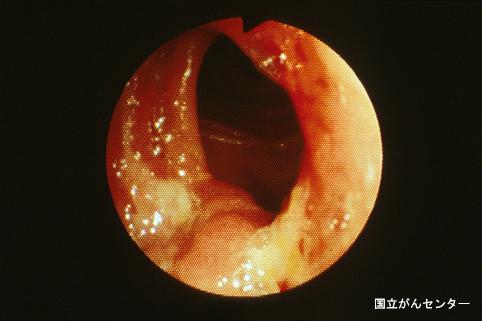

症例提示(所在地,施設名等): 東京都・ 国立がんセンター中央病院と九州がんセンターの共同作成

症例登録日 2003/09/01

画像数 10

性別 男性

画像ID:5639

疾患(病理主体)の分類悪性上皮性腫瘍/腺癌

部位(臓器別)2つ以上の臓器/

検査方法内視鏡

病変の最大径(ミリ)40以上